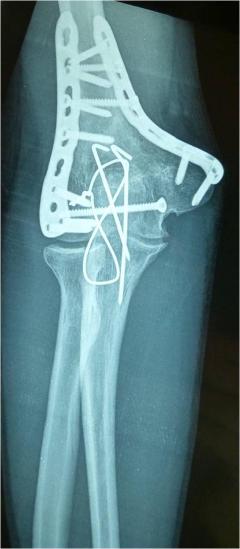

Περίπτωση 2ου ασθενούς

1 χρόνo μετά το χειρουργείο